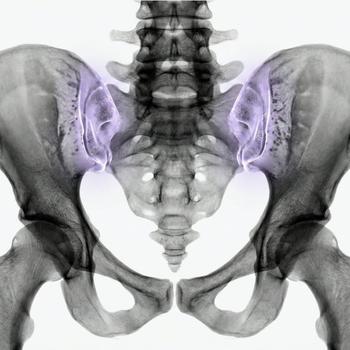

MRI Pelvic – for gynecological problems, cysts or suspected endometriosis

If you have pain in the lower abdomen, irregular bleeding, fertility problems or suspect that something is not right in the lower abdomen, an MRI examination of the pelvis can be the next step to get the right diagnosis. MRI pelvic, also called MRI gynecology, is a painless and radiation-free examination that provides very detailed images of both the uterus, ovaries and fallopian tubes.

The examination is used when other methods such as ultrasound or gynecological examination have not been able to explain your symptoms. With the help of MRI, conditions such as endometriosis, fibroids, cysts, tumors, malformations or effects on nearby organs such as the bladder or intestines can be detected. It is also an important method before fertility treatment or in preparation for surgery.

Whether you are seeking answers to long-term symptoms or following up on previous findings, pelvic MRI gives you and your doctor a clear picture that can form the basis for the right treatment and continued care.